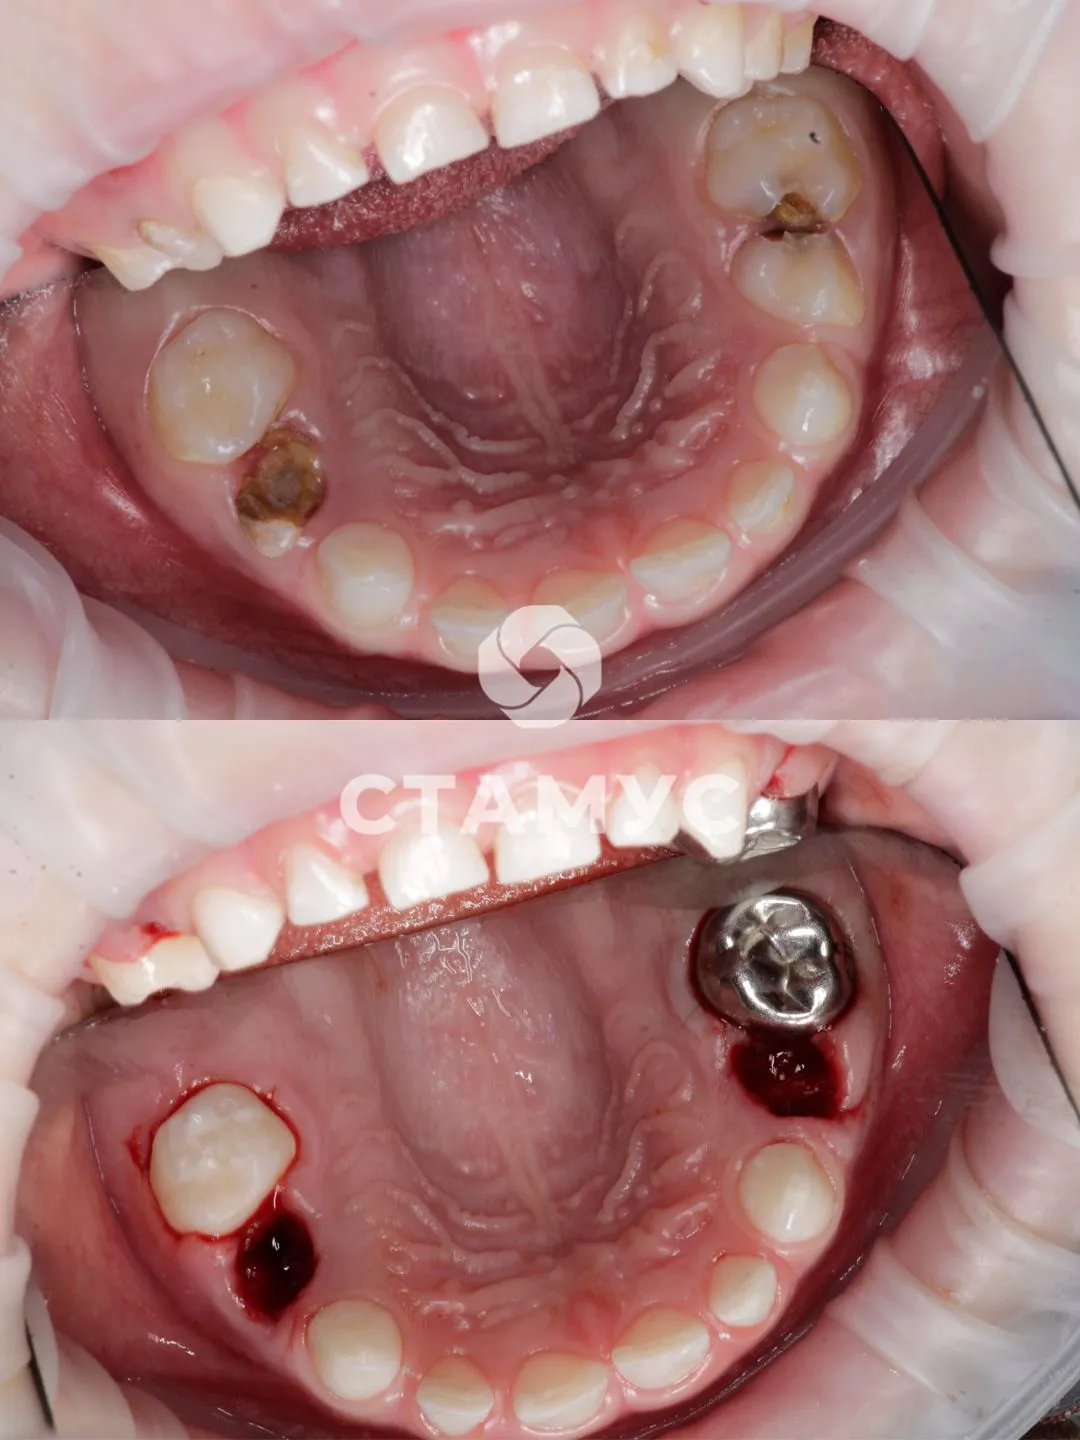

ребенку 6 лет, пульпит 3 зубов, кариес 5 зубов, удаление 2 зубов

Проведено лечение кариеса 5 зубов, пульпита 3 зубов, установлены 3 металлические коронки, запечатаны фиссуры зубов, удалены 2 зуба, выполнена профессиональная гигиена полости рта.